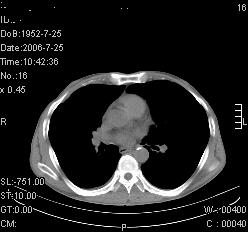

患者,男,54岁,咳嗦,咳痰20天。抗炎治疗2周。现esr76mm/h,目前患者症状明显好转,但发现两次ct片未见明显变化。两次分别做与7.25、7.31。第一次诊断右肺上叶炎症累计胸膜。大家看,从影像上内排除结核吗?

结核的可能性非常大,右上肺病变应该考虑干酪性肺炎。理由:

1.纵隔内多发淋巴结肿大。

2.esr76mm/h。

3.虽经抗炎治疗肺窗病灶有所吸收、减小,但纵隔窗病灶形态、密度、范围无明显变化。如果是单纯的大叶性肺炎,“抗炎治疗2周,目前患者症状明显好转”病灶应该基本消散了,至少也处于吸收消散期,密度变淡、范围变小。同时本病例所示其内的密度不均匀,见多发大小不一空洞样影也不符合大叶性肺炎吸收消散期表现。

病灶特点:片状 索条 结节混杂影,部分融合,密度不均,广泛累及相应胸膜.

临床治疗;二周未吸收.但症状好转.

多考虑:肺结核.